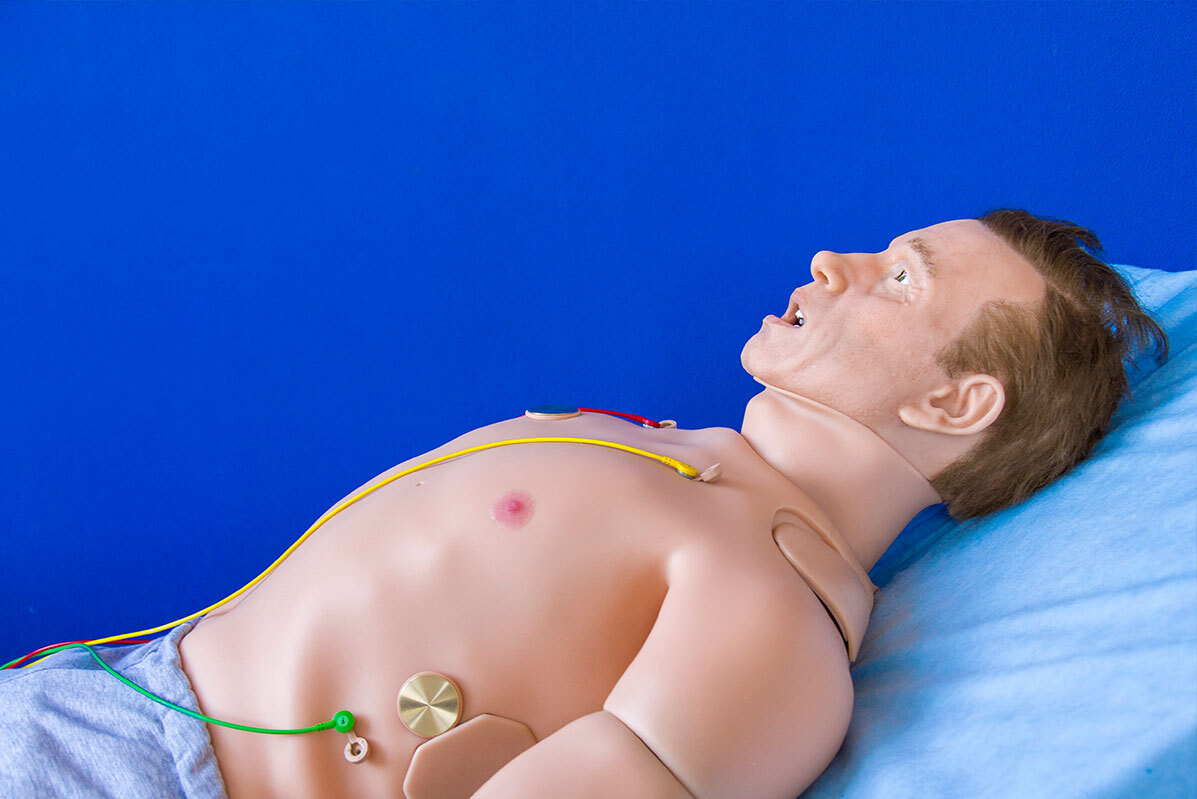

عملية زرع مع صمام خنزير قد تجنب مرضى القلب الجراحة العامة!

يمكن تجنيب المرضى الذين يعانون من حالة قلبية منهكة عملية جراحية كبيرة عن طريق زرع صمام إلكتروني.

وصمم الجهاز الصغير، الذي يمكن تركيبه في أقل من ساعة باستخدام مخدر موضعي، لعلاج قصور الأبهر، وهي حالة تؤدي إلى تجويع الدم المؤكسج في الجسم وتترك المرضى مرهقين.

وتحدث المشكلة عندما يتضرر الصمام الموجود عند مخرج القلب، الصمام الأبهري، ويفشل في الإغلاق التام. وهذا يسمح للدم بالتسرب للخلف إلى القلب ويؤثر على قدرته على الضخ بكفاءة. وهو الأكثر شيوعا عند المرضى الأكبر سنا والذين يعانون من ارتفاع ضغط الدم. وقد يكون الضرر أيضا بسبب العدوى.

وتتطلب الحالة جراحة القلب المفتوح، والتي تتضمن فتح صدر المريض، ووضع قلبه على آلة الالتفاف واستبدال الصمام.

ومع ذلك، يُترك العديد من المرضى أضعف من أن يتحملوا هذه الجراحة الكبرى. بالإضافة إلى ذلك، لم يكن هناك حتى الآن زرع صمام مصمم خصيصا لقصور الأبهر - يستخدم الجراحون غرسات مصممة لعلاج أشكال أخرى من أمراض الصمام.

تطوير جهاز قابل للزرع يذوب في الجسم عند انتهاء مهمته قادر على تخفيف الألم دون أدوية

ويمكن تركيب غرسة JenaValve Trilogy الإلكترونية الجديدة، التي تحتوي على إطار معدني وصمام من خنزير، خلال إجراء طفيف التوغل يستغرق أقل من ساعة. وقال طبيب القلب أندرياس بومباخ، الذي قاد الفريق الرائد في الجهاز في مستشفى سانت بارثولوميو في لندن: "لم يكن هناك شيء مثل هذا من قبل".

وستحدث ثلاثية JenaValve فرقا كبيرا. وتم علاج أول بضع مئات من المرضى الآن وكان هناك ما يقرب من 100% معدل النجاح.

وأثناء عملية زرع ثلاثية JenaValve، يتم إجراء شق صغير في الشريان الفخذي في الفخذ - يتم استخدام مخدر لتخدير المنطقة ولكن المرضى مستيقظون على نطاق واسع.

ثم يتم إدخال أنبوب دقيق ومرن يسمى القسطرة في الشريان ويتم تمريره عبر الجسم إلى القلب، باستخدام جهاز الأشعة السينية لمعرفة ما يقومون به في الوقت الفعلي. ويوضع JenaValve، المصنوع من إطار معدني على شكل أنبوب قابل للطي، في مكانه عبر القسطرة. وفي البداية يتم طيها، ولكن بمجرد أن يؤكد الجراح أنها في المكان المناسب، يتم فتحها.

وجرى توسيع الصمام بالكامل، ويبلغ قطره حوالي بوصة واحدة، ولكن يمكن تعديل الحجم في الموقع للتأكد من أنه مناسب تماما. وقال البروفيسور بومباخ إن ثلاث أرجل صغيرة - تشبه إلى حد ما الأرجل الموجودة على وحدة الهبوط على سطح القمر - تثبتها في موضعها فوق الصمام الأورطي الطبيعي، وتبدأ في العمل على الفور.

ثم يتم إزالة القسطرة وخياطة الشق والسماح للمرضى بالعودة إلى المنزل بعد يوم أو يومين.

المصدر: ديلي ميل